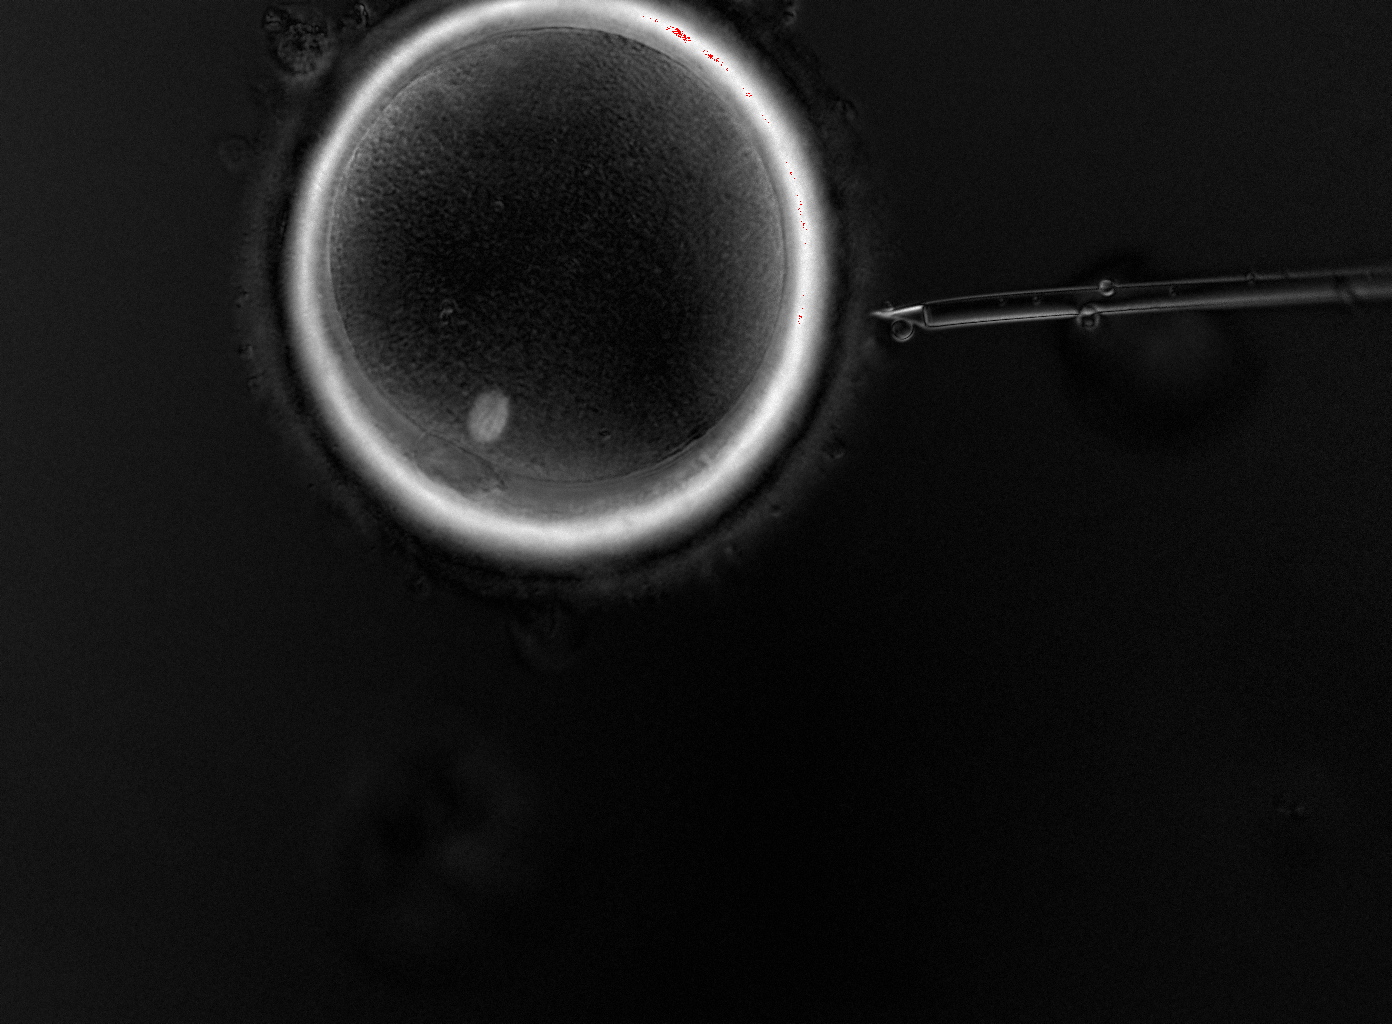

All fertilisation at HOPE is performed using ICSI — direct injection of a single sperm into the egg — which provides the highest fertilisation success rate. Infertility is not limited to one partner, and our laboratory is equipped with specialised techniques to address even the most complex forms of male infertility: from careful sperm selection based on morphology and laboratory assessment, to cell activators for cases of limited sperm motility, to surgical sperm retrieval (TESE/TESA) when sperm cannot be obtained through standard methods.

Together with your doctor, our embryologists perform the transfer of the selected embryo into the uterus. We prepare the embryo and remove it from the incubator only when the doctor has confirmed smooth access to the uterine cavity — minimising the time the embryo spends outside its controlled environment. When clinically indicated, we perform assisted hatching — a precise incision in the embryo's zona pellucida — to support implantation.